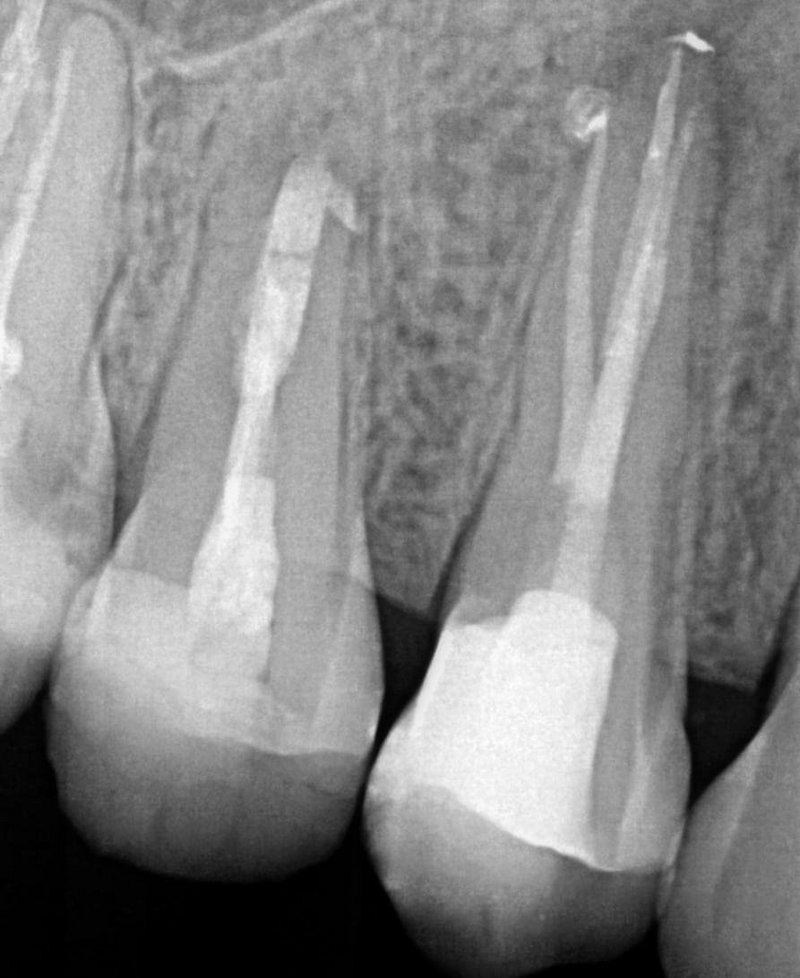

Bei einer klinischen Nachkontrolle zwei Wochen postoperativ im Rahmen der Weiterversorgung gab die Patientin an, keinerlei Beschwerden oder Schmerzen nach der Wurzelkanalfüllung gehabt zu haben. Die technisch einwandfrei verlaufende Behandlung darf auf eine baldige knöcherne Ausheilung hoffen lassen. Eine erste radiologische Nachkontrolle ist in sechs Monaten geplant. Für eine langfristig gute Prognose wird der Zahn zeitnah mit Zahnersatz aus dem hauseigenen Labor versorgt. Die Patientin bedauerte im Nachgespräch, für die Wurzelbehandlung nicht von Anfang an eine Praxis mit entsprechender technischer Ausstattung und spezialisierten Zahnärzte aufgesucht zu haben. Sie zeigte sich sehr erleichtert, dass der Zahn nicht extrahiert werden musste. Im Anschluss an die beschriebene Behandlung wurden zwei weitere Revisionen an Zahn 15 und 16 im AllDent Zahnzentrum Bremen durchgeführt.